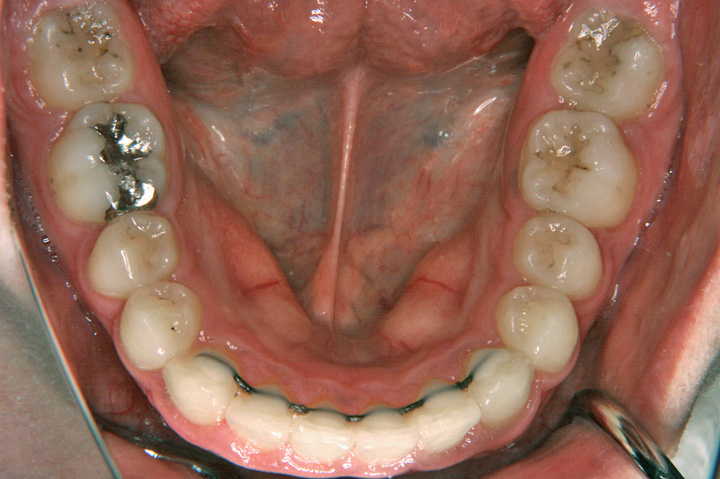

出っ歯を主訴に来院された女性の患者さんです。上下顎前歯部に叢生があったため、上顎両側小臼歯2本を抜歯し、バイヘリックスを装着し下顎歯列を側方拡大することで、歯の排列スペースを獲得しました。上下エッジワイズ装置により治療し、良好なprofileを獲得しています。ボンデッドワイヤーとリテーナーを併用した保定に移行しています。